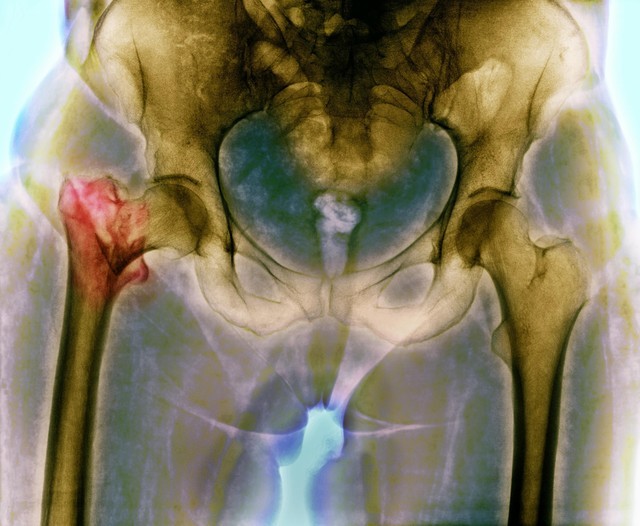

真正影响生育的,是骨盆的形状和宽度。

骨盆是胎儿出生时必须通过的通道,其宽窄程度直接影响分娩的顺利程度。

有研究显示,骨盆内径较宽的女性,顺产的几率确实更高。

然而,骨盆宽并不等于屁股大。

有些女性的骨盆宽而臀部脂肪较少,看起来并不“丰腴”,但生育条件很好;

也有些人虽然臀部脂肪堆积,但骨盆却相对狭窄,并不一定适合顺产。

所以,屁股大只是外在表象,骨盆健康才是决定生育能力的重要因素。

虽然屁股大和骨盆宽不能划等号,但骨盆健康却确实对分娩影响重大。

宽敞、对称的骨盆更有利于胎儿顺利通过产道,减少生产时的风险。

如果骨盆形态不佳,比如畸形或发育不良,则可能增加难产的几率。